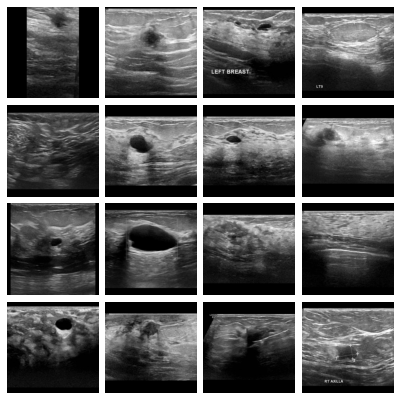

- bus, Breast Ultrasound:

Dataset of breast ultrasound images of women between 25 and 75 years old, derived from the Breast Ultrasound Images Dataset [al-dhabyani_dataset_2020]. The 780 original images were converted to grayscale and their masks to binary format. Images and masks were zero-padded to a square shape and resized to pixels using bi-cubic interpolation and nearest neighbor interpolation respectively (no images were up-scaled). The multi-class tumor classification task with normal, benign, and malignant examples was adopted without modifications from the source dataset. We additionally defined a binary classification task between malignant tumors and other images.